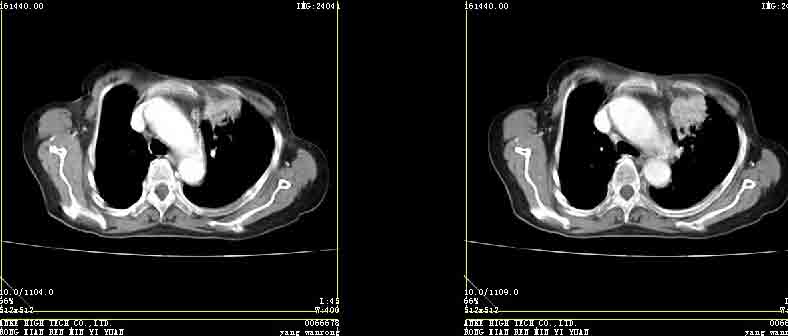

女77岁因左侧胸痛伴咳嗽入院;提示:病灶平扫45hu,强化145hu补充:双肺内未闻及干湿罗音

考虑纵膈型肺癌并转移。

考虑纵膈型肺癌并转移

强化密度略高于肌肉 考虑周围型肺癌【小箭头为容积效应现象】

左上肺前段可见分叶团块影,强化明显,周围见带状不张影,右肺结节,左肺沿肺纹模糊片状影,考虑左上肺占位,肺癌可能性大。

考虑左肺上叶前段肺癌伴节段性不张、肺内转移,建议薄层扫描。